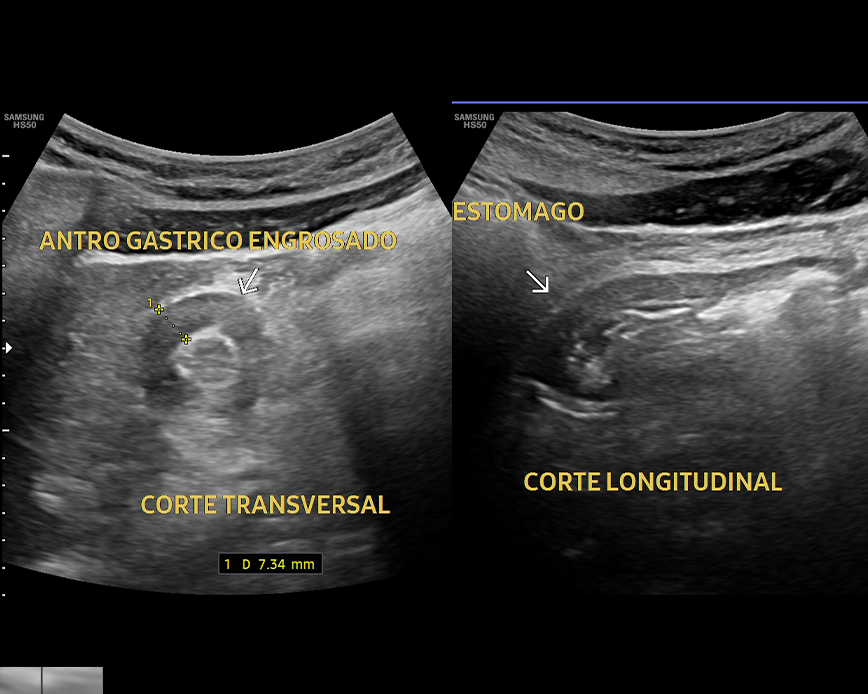

- Evaluación del dolor abdominal

- Evaluación del páncreas